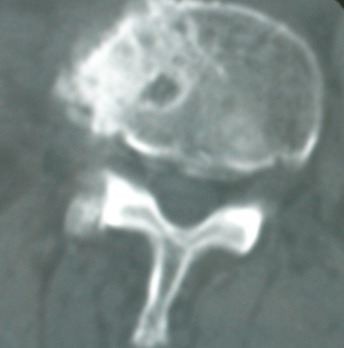

以下是引用卜一在2008-6-3 19:33:00的发言:[br]双肺结节,以双上肺分布为多,期间搀杂片状致密影及索条致密影。考虑:继发性肺结核伴血型播散可能性大。不除外肺泡ca的可能!另:椎体退变!

以下是引用panyishengct在2008-6-3 21:09:00的发言:[br]双上肺弥漫性小结节影,纵隔窗内钙化淋巴结影,考虑矽肺或/和tb可能性较大,不除外肺ca可能。腰椎考虑退变。 [br][br]